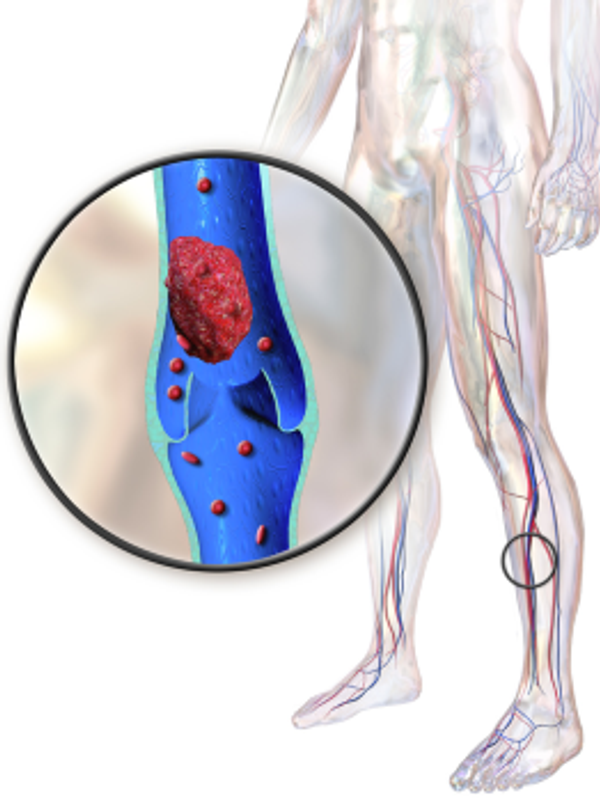

Soms vindt er bloedstolling plaats terwijl er geen noodzaak voor is; er is geen wondje dat moet genezen. Er vormt zich dan een stolsel in een bloedvat ergens in het lichaam, dat de bloeddoorvoer in het bloedvat geheel of gedeeltelijk blokkeert. In theorie kan zo’n stolsel overal in het lichaam ontstaan. Hierdoor heeft een stolsel ook verschillende gevolgen.

Een stolsel in een slagader (arteriële trombose) kan onder andere leiden tot een hartinfarct, een beroerte of tot een verstopping in het been. Zit een stolsel in een ader (veneuze trombose) dan kan dit voorkomen in oppervlakkige of dieper gelegen aderen. Oppervlakkige veneuze trombose zien we vaak in spataders en diepe veneuze trombose zit in de diepere vaten, meestal in het been.